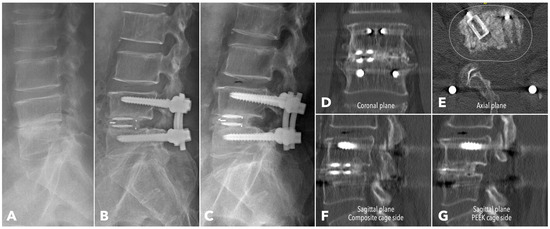

Lumbar spine computed tomography (CT) with 3 mm thin-slice coronal and sagittal reconstructions was performed one year after the surgery. Fusion status was assessed using the Bridwell grading system based on bone window images (Figure 4). Grades I and II were defined as successful fusion. Cage subsidence was defined as sinking > 2 mm beyond the bony endplate [24,30]. The presence of subchondral osteolysis was also recorded as a potential indicator of pseudoarthrosis (Figure 5).

Figure 4. Postoperative 1-year CT reconstruction to evaluate the Bridwell fusion grade. (A) Grade I solid fusion with remodeling of the trabeculae. (B) Grade II fusion with bridging bone formation and no radiolucency between the cages and the endplates. (C) Grade III fusion with radiolucency between the bone graft and endplate. (D) Grade IV fusion with resorption of the bone graft.